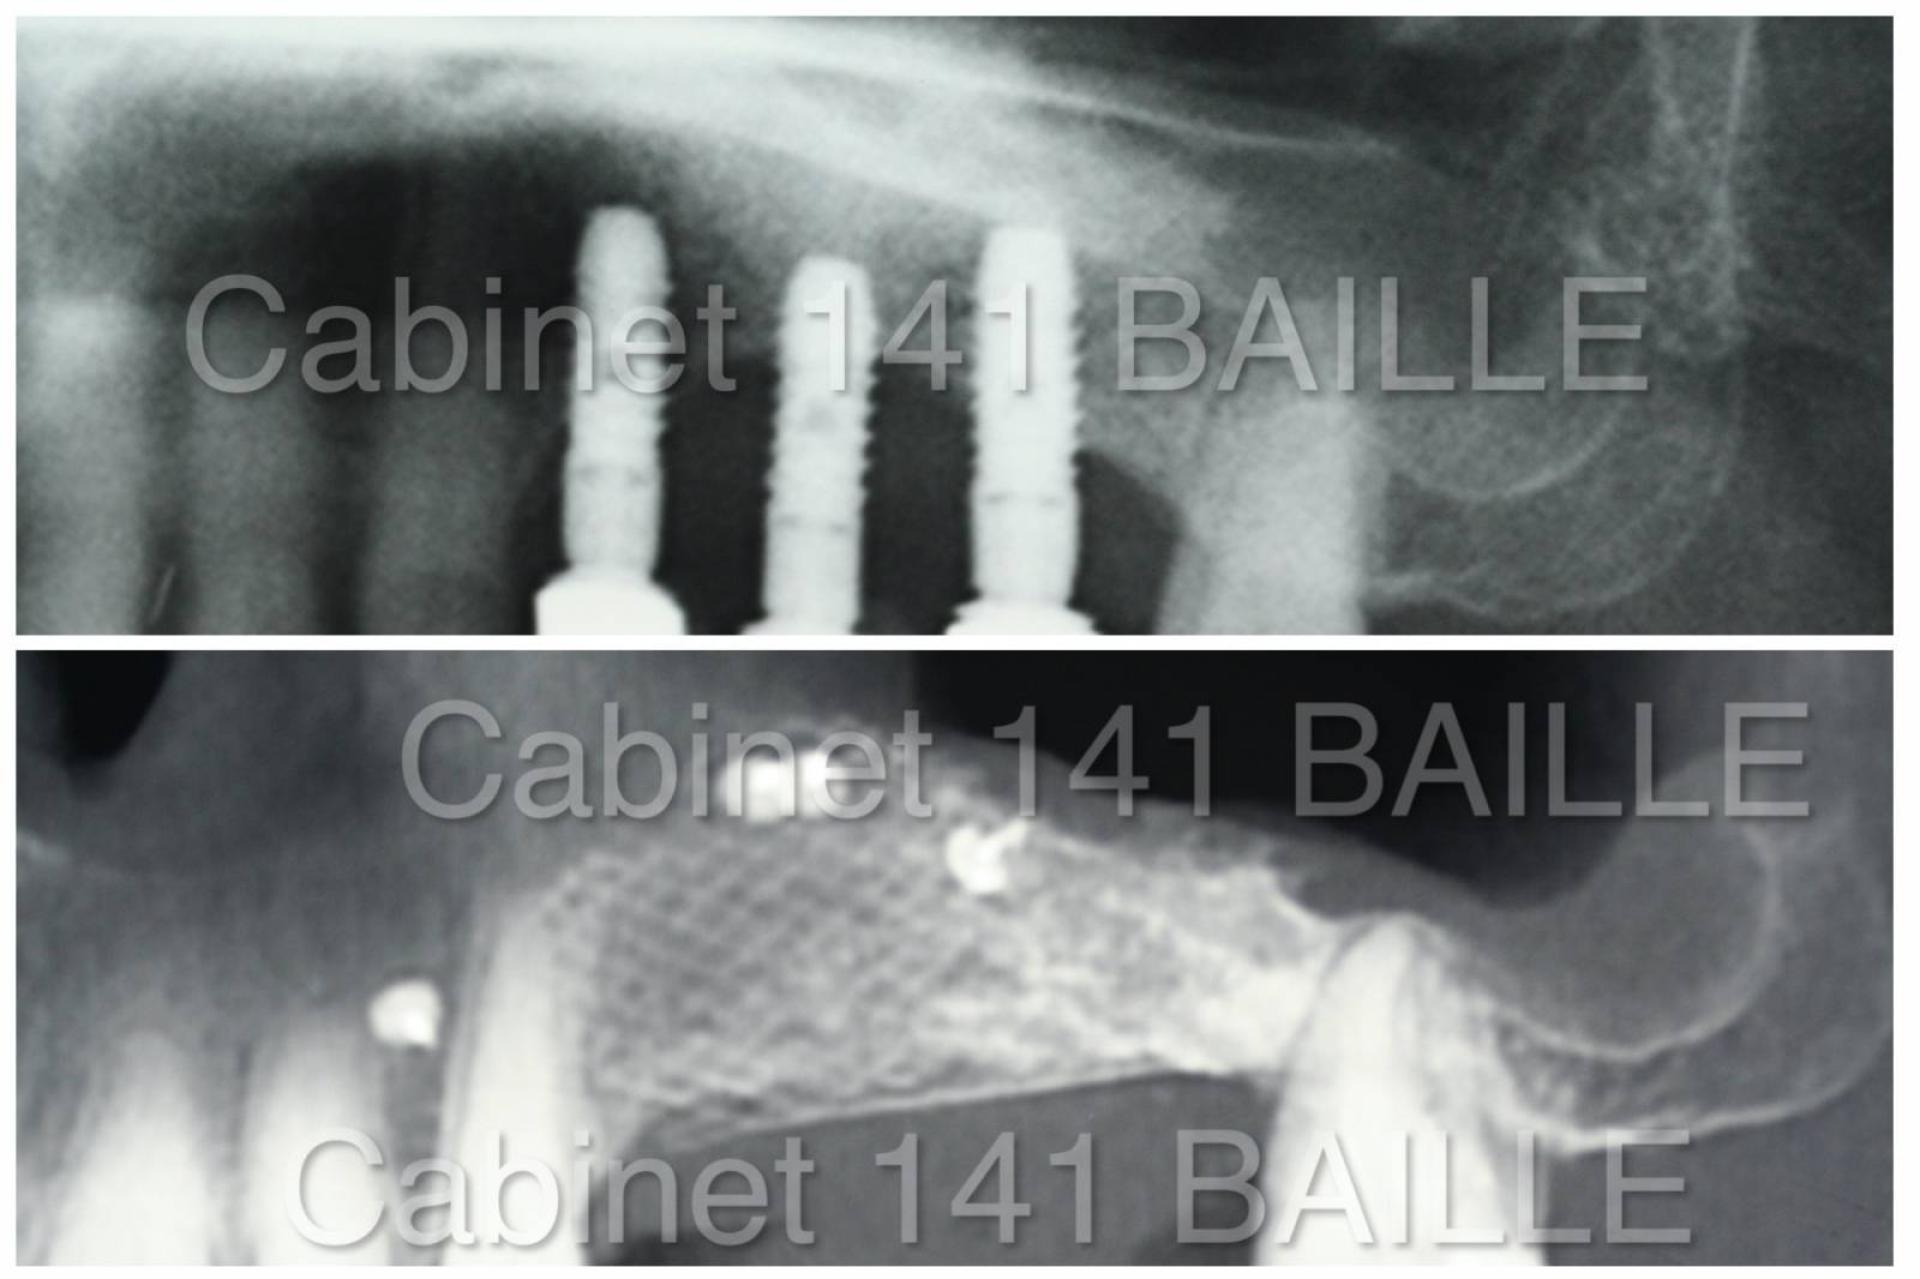

spécialiste de technique de ROG implantaire dentaire marseille

Régénération osseuse Guidée en Implantologie R.O.G .Dr Tourrolier Marseille.

La régénération osseuse guidée permet de faire des augmentations de volume osseux avant de mettre en place des implants dentaires en greffant de l'os sur le maxillaire.Explications du Dr Tourrolier Didier.